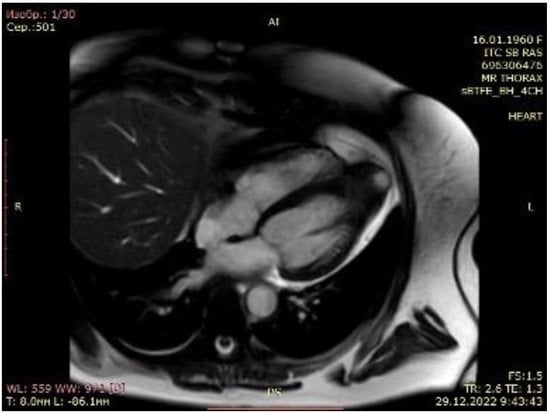

2.1. Case Scenario

2.2. Surgical Procedure

3. Results